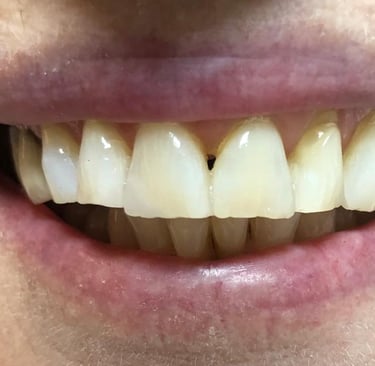

Aspecto Clínico Final - Fotografias originais — nenhuma contém retoques — A cor dos dentes é escolhida de acordo com o gosto e a preferência estética de cada paciente.

Depois

Depois - Restauração em resina associada ao clareamento dental.